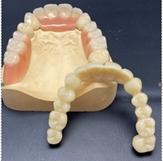

Bis 2017 wurden in unserem Labor die Teleskoparbeiten im klassischen Gussverfahren hergestellt. In den vergangenen Jahren haben wir viel positive Erfahrungen mit der Herstellung taktil gescannter Primärkronen und aus einem Blank gefräßter Sekundärkonstruktionen gesammelt.

Bei uns werden die Arbeiten nicht als Klemmpassung, sondern als Saugpassung gearbeitet.

Wir haben das große Glück, dass wir hier bei uns im Hause eine Informatikerin eingestellt haben, die gleichzeitig auch Zahntechniker ist. Diese Mitarbeiterin kann also beides – für diese Arbeit essentiell wichtigen Daten erfassen, verar-beiten und dann auch noch dentaltechnisch umsetzen. Die Primär- und Sekundärkronen werden so gestaltet, dass ein Saugeffekt den festen Halt des Zahnersatzes sichert.

Durch die Nutzung eines taktilen Scanners werden die Daten der Primärkronen präzise abgetastet und erfasst. Beim taktilen scannen profitieren Sie von einem optimalen Sitz Ihrer Teleskoparbeiten. Dieses gewährleistet eine qualitativ höchstmögliche Versorgung Ihrer Patienten.

Die im Anschluss in unserer hauseigenen Fräsanlage entstanden Sekundär-konstruktionen gewährleisten die perfekte Passung.

Auf Wunsch können Friktionselemente (TK-soft) eingearbeitet werden. Mit TK-soft kann die Haltekraft der Prothese sehr fein stufenlos reguliert und immer wieder nachaktiviert werden. Damit ist eine individuelle Anpassung an den Friktionswunsch des Patienten machbar. Weitere Vorteile sind, dass diese kostengünstig eingearbeitet werden können und kein Kleben oder Löten notwendig ist.